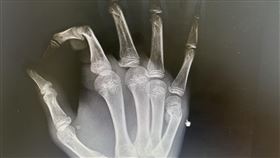

林郁婷奪金 國中生激動捶牆竟拳擊手骨折

「台灣拳后」林郁婷成功奪下巴黎奧運57公斤女子拳擊金...